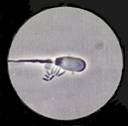

AI sperm normal

The normal sperm with a tail central to the head.  The tail is straight without any kinks.  The head is a smooth even head.